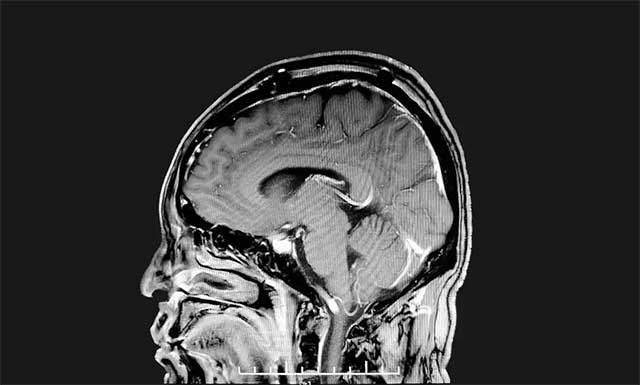

▲ 肿瘤已被切除

沈建康教授聚精会神、抽丝剥茧般一点点游离肿瘤包裹的静脉,再以超声刀切除残余肿瘤组织,历时四个多小时,手术顺利完成。术后经病理分析,该肿瘤为脑膜瘤,与术前诊断相一致。